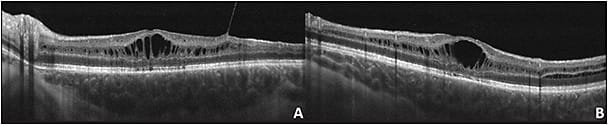

Imaging findings with SD-OCT of the fovea (Figure 1) showed cystic maculopathy in all included eyes. Cysts were found in the inner nuclear layer in all eyes, outer plexiform layer in 4/11 (36%) eyes, outer nuclear layer in 5 (45%) eyes, and ganglion cell layer in 1 (9%) eye. In all 11 eyes there was distortion of the vessel architecture in the superficial capillary plexus. In 9 eyes, there was no appreciable foveal avascular. In all cases, there were avascular cystic cavities surrounded by vessels in a petaloid-like shape in the deep retinal plexus. There were no telangiectatic vessels or aneurysmal dilations identified. The choriocapillaris was within normal limits in 11/11 eyes (Table 1).

In this study, the OCT and OCTA characteristics in XLRS were examined. In prior OCT studies of XLRS, there have been inconsistencies regarding the specific retinal layer in which the schisis occurs. Histopathologic studies observed schisis in the nerve fiber layer.16,17 However, further studies using SD-OCT have shown schisis in the outer retinal layers as Gregori et al5 reported a case series in which the splitting was primarily in the inner nuclear layer and in the outer plexiform layer. This is similar to the results in the current study, where cystic changes were found in the level of the ganglion cell layer in 1 eye (9%), in the inner nuclear layer in 11 eyes (100%), in the outer plexiform layer in 4 eyes (36%), and in the outer nuclear layer in 5 eyes (45%).